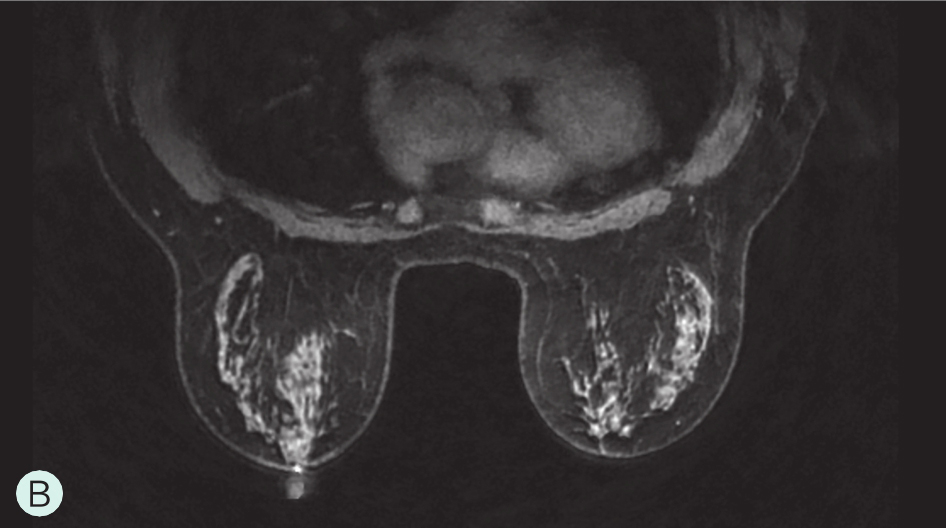

图1-3-3 乳腺MRI不同乳腺密度

A.脂肪型;B.散在致密型;C.不均匀致密型;D.极度致密型